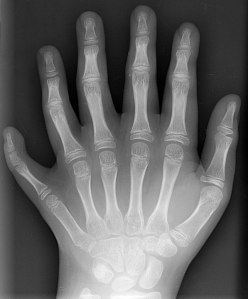

Hand study projects of inquiry: Explore hands with children. Research the structure and purpose of hands. Have the children ask and answer and consider questio

ns such as, “What can my hands do? What can we use hands for? How are hands the same or different?” Investigate the bones and muscles of hands. This type of project of inquiry can lead to meaningful and authentic arts learning experiences, including but certainly not limited to the ideas listed here.